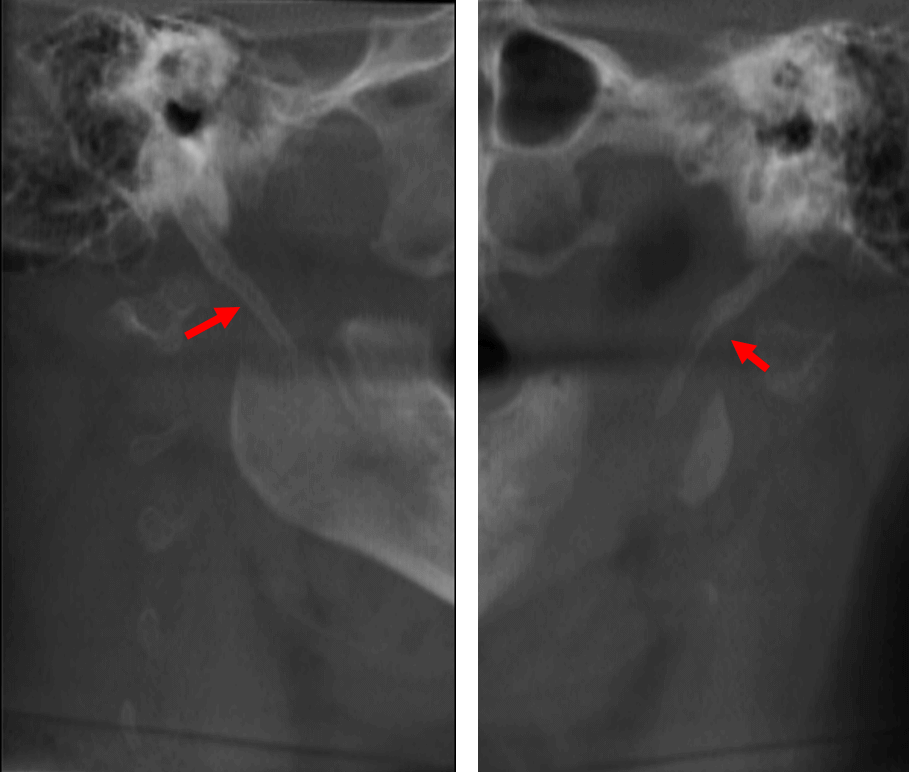

En la evaluación con tomografía computarizada cone beam, en el corte coronal (Fig.1) se observa un elongamiento o extensión de la apofisis estiloides de ambos lados, evidenciando un patrón de calcificación segmentado en el lado derecho.

En cortes tangenciales (Fig.2) se observa el elongamiento de la apofisis estiloides o la mineralización del tercio superior del ligamento estilohioideo en ambos lados.